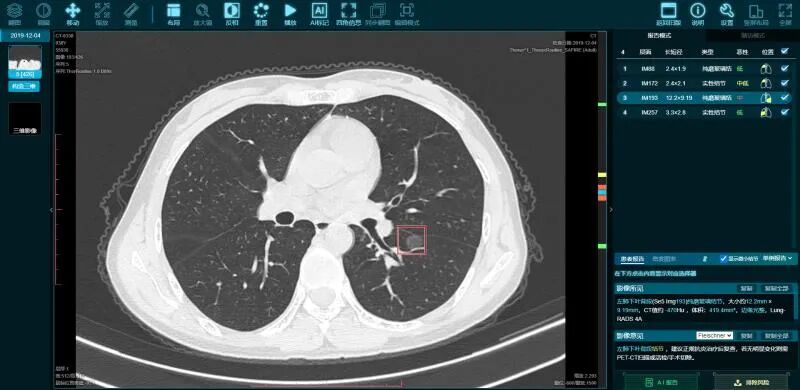

医准智能肺部CT智能检测系统根据CT影像中肺部结构特征及肺结节特征,利用人工智能深度学习理论建立算法模型,自动检测肺结节,分析结节解剖位置、场景、体积、结节类型、提供结节良恶性分析参考及影像建议,高结节检出率,低假阳性率为医生诊疗提供精准高效的临床建议,有效提高医生阅片效率。